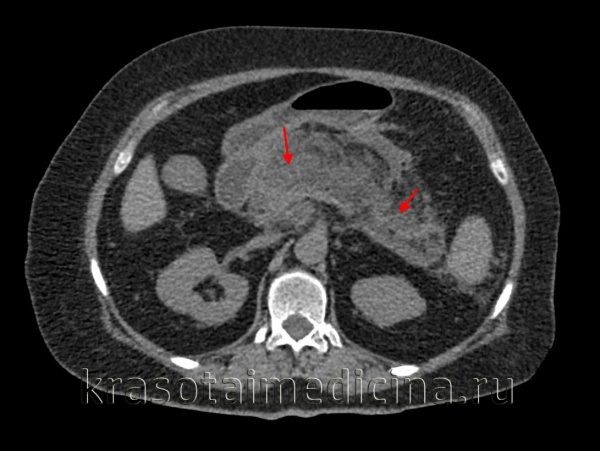

Наиболее информативными инструментальными методами диагностики острого панкреатита являются УЗИ, КТ, МРТ органов брюшной полости. УЗИ остается одним из наиболее доступных и информативных методов исследования. Эта безопасная неинвазивная методика позволяет выявить этиологический фактор острого панкреонекроза (конкременты желчевыводящих путей), отек и участки некроза поджелудочной железы, позволяет дифференцировать жидкостные образования. Но «золотым стандартом» диагностики на современном этапе является компьютерная томография органов брюшной полости. Данная методика позволяет четко визуализировать увеличение поджелудочной железы, очаги некроза, а также наличие осложнений, с высокой достоверностью разграничивать жидкостное скопление от плотных некротических масс. Наличие пузырьков газа в зоне деструкции, определяемое при КТ-исследовании, свидетельствует об инфицировании данного очага.

Компьютерная томография является более точным методом диагностики острого панкреатита по сравнению с УЗИ. Для проведения ее нет помех. Достоверность диагностики увеличивается при усилении контрастным материалом. Компьютерная томография с усилением позволяет более четко выявить диффузное или локальное увеличение размеров железы, отек, очаги некроза, скопление жидкости, изменения в парапанкреатической клетчатке, "дорожки некроза" за пределами поджелудочной железы, а также осложнения в виде абсцессов и кист.